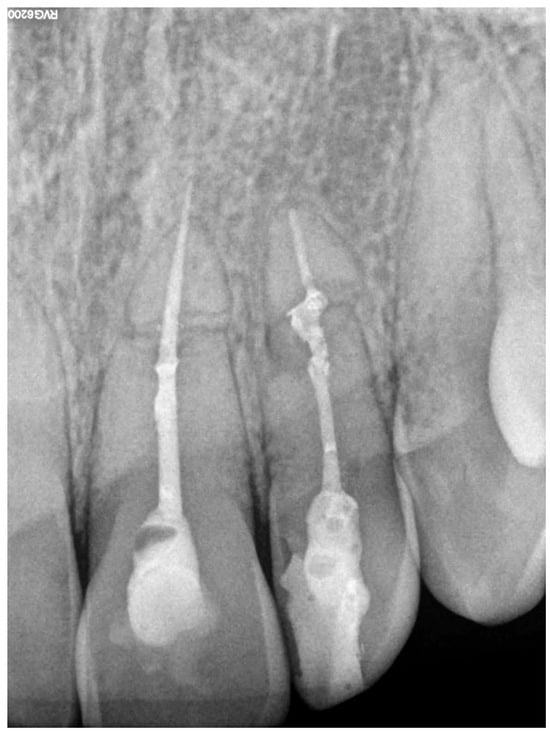

A 19-year-old female patient reported to the Department of Conservative Dentistry Medical University of Gdańsk due to pain in tooth 22 (upper left lateral incisor, according to the Federation Dentaire Internationale (FDI) dental numbering system) and 21 (lateral left incisor) [14]. In her medical history, it was noted that she suffered an injury in 2021 after being hit by a car while riding her bicycle, which resulted in a two-week traumatic coma and a diagnosis of a traumatic brain injury. Following this incident, the patient was referred for outpatient treatment and dental consultation. During the dental examination, pathological mobility (Grade 2) (Miller’s index of mobility) [15] was observed in teeth 11, 21, and 22. Teeth 12, 21, and 22 appropriately responded to electrical stimuli, while tooth 11 showed no reaction to the Pulp tester (Yusendent, China). Radiographically, a Class VI injury according to the Ellis Classification [16] was identified in teeth 21 and 22, and a Class VII injury in teeth 12 and 11. The patient was informed about the necessity of follow-up visits; however, she did not attend. In April 2024, the patient returned complaining of pain in teeth 21 and 22. She described the pain as constant, occurring when biting, worsening with hot foods, and lasting at night. Clinical examination revealed pain upon vertical percussion and no reaction to electrical stimuli. The buccal mucosa of the alveolar process was found to be without clinical changes, and there was no tenderness when palpating the alveolar process. Radiovisiography (RVG) (Carestream 9300C, Carestream Dental, 2018, Atlanta, GA, USA) did not show any periapical changes. Notably, the RVG revealed a complex root fracture in tooth 22, characterized by a double fracture line and two distinct root fragments (Figure 2a), which is generally an indication of tooth extraction. However, due to the young age of the patient and the psychological aspect, it was decided to perform conditional endodontic treatment. The patient was informed about the possibility of treatment failure and the need for extraction. The patient accepted the presented treatment plan. During a pain emergency visit, an attempt was made to trepan teeth 21 and 22 under infiltration anesthesia with Dentocaine (40 mg/0.01 mg/1 mL, 1 ampoule, Inibsa, Madrid, Spain); however, the canal in tooth 22 was not locatable. A temporary filling (Kromoglass 2 (20 g) Lascod, Milano, Italy) was placed, and tooth 22 we classified for treatment utilizing an endodontic guide.

Figure 2. RVG of tooth 22 (a) before treatment, (b) during treatment (with instrument in canal), (c) after treatment (canal filled with gutta-percha and AH Plus).

This software allowed for the preparation of the file for 3D printing by adding supports and slicing the template into layers of 50 µm thickness. The template was then printed using dedicated transparent resin—Class IIa (NextDent SG, Istanbul, Turkey) on a 3D printer (Phrozen Sonic Mini 4K, Taipei, Taiwan) [18,19]. The post-processing phase was conducted in strict conformity with the resin manufacturer’s instructions to prevent dimensional alterations [20]. The placement of the template in the oral cavity was checked, and the treatment area was isolated. The patient was locally anesthetized with infiltration using Dentocaine (1 ampoule, Inibsa, Madrid, Spain). The temporary filling was removed from tooth 22. The template was placed on the upper arch, and canal access was initiated using a Munce bur #1 (Munce Discovery BurTM). The template was removed after the bur reached a depth 2 mm greater than previously planned, to irrigate the root canal with a 5.25% NaOCl solution, allowing for endodontic access control and cleaning of the Munce bur. The work continued until the bur achieved the planned length previously set. The position of the canal was checked using C-pilots (VDV, Munich, Germany) ISO 10 and ISO 15. Following that, RVG was performed (Figure 2b) to confirm the correct position of the instrument in the canal and the length of the canal. The canal was prepared using Reciproc Blue (VDV, Munich, Germany) endodontic instruments to the working length, confirmed by measurements with an endometer (Raypex 5, VDW, Munich, Germany) and radiographically. The canal was irrigated using protocol along with ultrasonic activation (PUI) with 5.25% NaOCl, 40% citric acid, and triple-distilled water. After drying the root canal with a paper point (Reciproc 25, VDV), the canal was filled with gutta-percha by a Continous Wave Obturation (CWO) (Reciproc 25, VDV, and BeeFill 2in1 Obturation Kit, VDW GmBH, Munchen, Germany) with the sealer AH Plus (Dentsply DeTrey GmbH, Philadelphia, PA, USA). After filling the canal, RVG (Figure 2c) and CBCT imaging (Figure 3b) were performed to verify the accuracy of the canal filling. Finally, a permanent composite filling (Gradia Direct, GC, Tokyo, Japan) was placed. The patient returned for follow-up visits at 3 and 6 months, reporting a complete resolution of pain. Clinically, there was no pain upon vertical percussion, and there was no tenderness upon palpation of the alveolar process. The buccal mucosa presented without clinical changes. The mobility of the tooth was within the physiological limits (Grade 1 Miller mobility index) [15]. Radiographically, there were no signs of external resorption or inflammation around the tooth fragments and there were no periapical changes observed. The patient was advised to continue with regular follow-ups. At the 12-month follow-up visit, the patient exhibited no deviations from normal clinical findings. The examination revealed consistent results with the previous visit, showing no signs of discomfort, tenderness, or radiographic abnormalities (Figure 6 and Figure 7). The patient was informed about the need for further regular check-ups and to urgently report for a visit in case of any disturbing symptoms, such as recurrent pain, increased tooth mobility, or swelling.